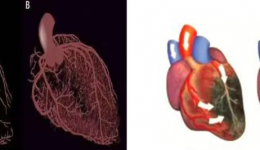

近日,宋先生(化姓)因心脏不适来我院进行超声心动图检查时,医生发现其室间隔上部存在连续性中断,三尖瓣隔瓣与室间隔缺损的右室面黏连,并在瓣尖部观察到5mm的缺损,缺损上缘距离主动脉右冠瓣仅2mm。未发现主动脉瓣脱垂和反流(见图一)。于是,...